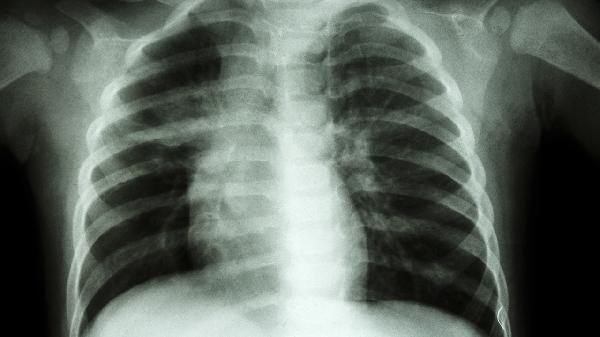

肺尖部肿瘤或淋巴结肿大可能从下方挤压胸廓出口。这类患者往往伴有咳嗽、消瘦等全身症状,需通过CT明确诊断。治疗原发病同时,可短期使用加巴喷丁胶囊控制神经痛。典型表现为夜间症状加重无法平卧。